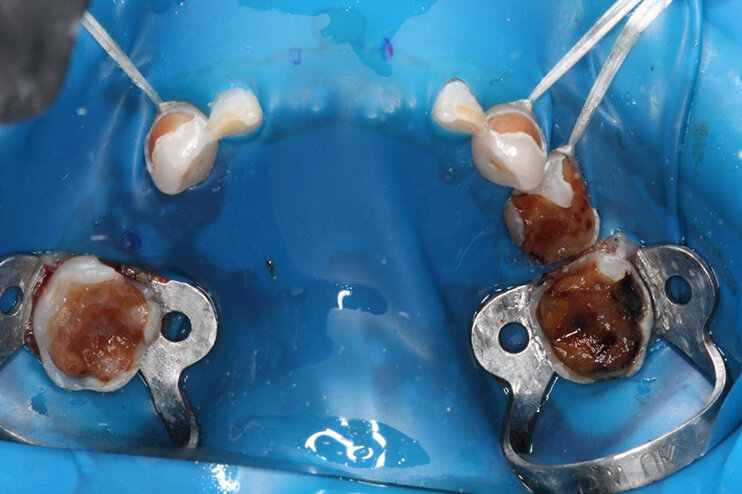

Сложный случай удалось решить детскому стоматологу-терапевту клиники НовоДент на Тольятти, 70а — Ждановой Алине Владимировне. На осмотр поступила малышка в возрасте 5 лет. Все молочные зубки были поражены кариесом. Спасти их можно было, только используя современный протокол. Посмотрите на фото масштабы поражения.

Во-вторых, лечение по мировым стандартам предполагает использование коффердама — стоматологического латексного платка, изолирующего зубы от крови, слюны и других жидкостей. Это помогает полечить зуб в стерильных условиях, не допустить попадания новых микробов, а значит увеличить шансы довести молочные зубки до естественной физиологической смены на постоянные зубы без нового кариеса.

В-третьих, лечение детских зубов в клинике НовоДент на Тольятти 70а проводится с использованием оптики. Доктор видит область лечения во всех деталях, а потому очищение зуба от кариеса проходит максимально качественно.

В-четвертых, детские стоматологи НовоДент прекрасно восстанавливают зубы с помощью коронок. Если молочный зуб разрушен на 50%, то также как и у взрослых, по современным стандартам, он должен быть закрыт коронкой (если по старинке, то зубу светит только удаление).